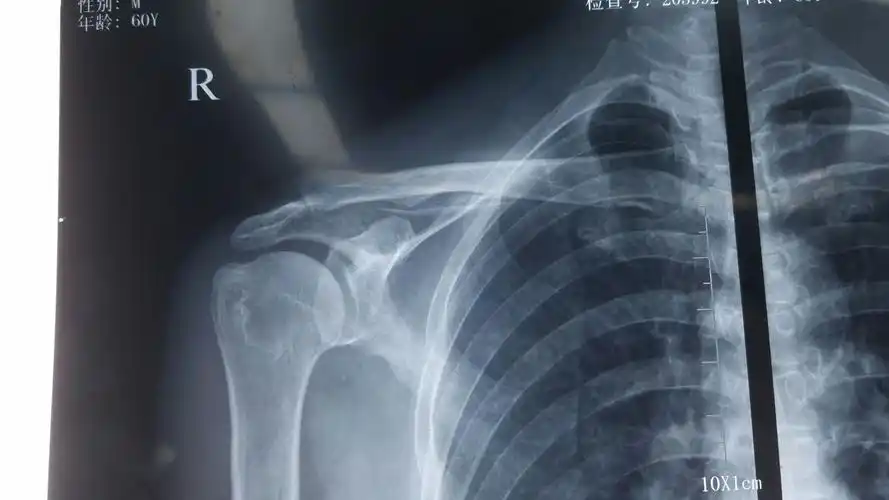

肩关节正位

术前左肩关节正位片提示:左肱骨大结节处骨赘形成(肩峰撞击引起)